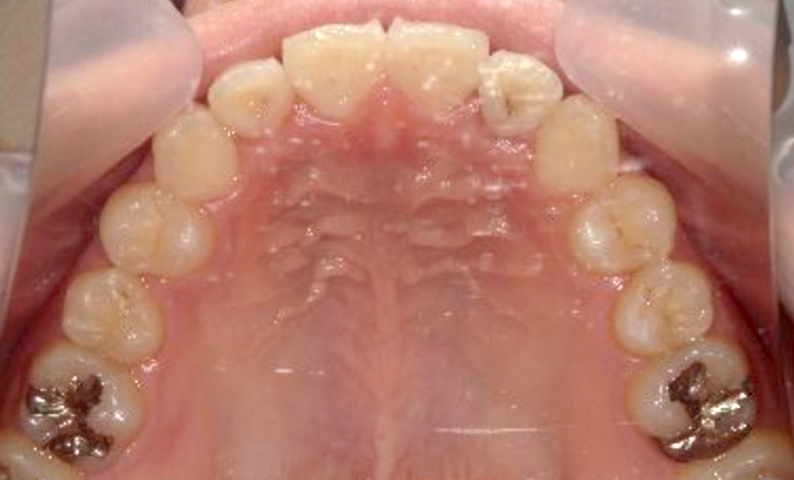

症例_005 上下顎の部分矯正

治療期間:11ヶ月金額:54万円+税女性前歯のガタガタ捻転歯

| Before | After |

|---|---|

|